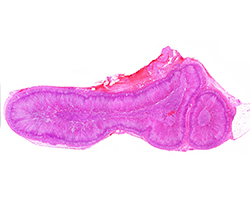

Digestivo II. Tubo

Digestivo II. Tubo

Esófago, estómago, intestino delgado y grueso y apéndice.

(19 preparaciones) -